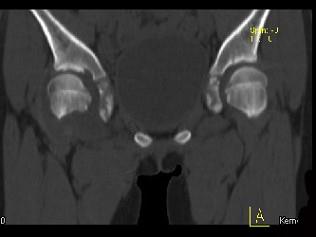

问题 女,11岁,肺部有结核病史,2个月前右髋关节有外伤史,右髋关节部逐渐肿胀疼痛,休息后可减轻,请结合所提供图像,选择最佳选项 ( )

选项 A、右髋关节类风湿关节炎 B、右髋关节痛风 C、化脓性骨关节炎 D、右髋关节退行性变 E、右髋关节结核

答案 E